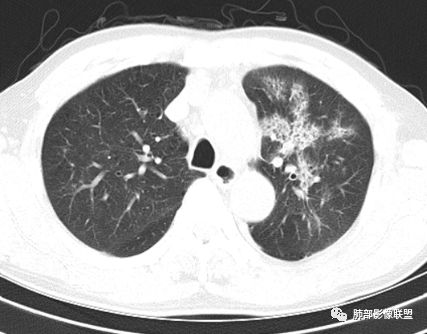

鳞癌起源于支气管粘膜,是气道中最常见的恶性肿瘤,易造成支管壁增厚,并突入腔内形成结节,造成狭窄、阻塞或截断;早期鳞癌表现为沿支气管生长的梭形结节或局限性增厚,辖区内常出现阻塞性炎症,这样的病灶赢多平面重建并仔细观察支气管改变;如果有支气管壁偏心性增厚伴管腔狭窄或腔内结节形成,都要想到早期鳞癌的可能性,复查或内窥镜检查是必要的。

鳞癌好发于中老年人,与吸烟关系密切,如果发现不易吸收的,或同一部位反复无常局限性肺炎,我们应当仔细观察支气管壁的病变除外阻塞的可能;该病例右肺下叶背段及左肺上叶支气管有肿块及管壁的增厚,应当想到恶性可能。

2.左肺上叶大范围高密度影,几乎占据整个肺叶,没有体积改变,尽管小叶间隔显示明显,但初诊还是首先会想到社区肺炎,尤其是结合患者有发热及左侧胸痛的临床表现。

会是粘液腺癌吗?如此大范围,又在上叶,周围却未见向外飘散的结节影,难以想象。

3.我们都注意到患者左肺上叶支气管开口的改变,这种改变有可能会用常见的“肉芽肿性炎”或“分泌物”加以解释,因管腔内的隆起部分未能观察到强化,管壁外未见相应快影或结节影。

熟料问题恰恰出在这里!它没能引起完全阻塞,未能形成“S”形肺不张。

该病例非常值得我们警醒,忽略支气管管腔内的任何异常都可能大意失荆州!